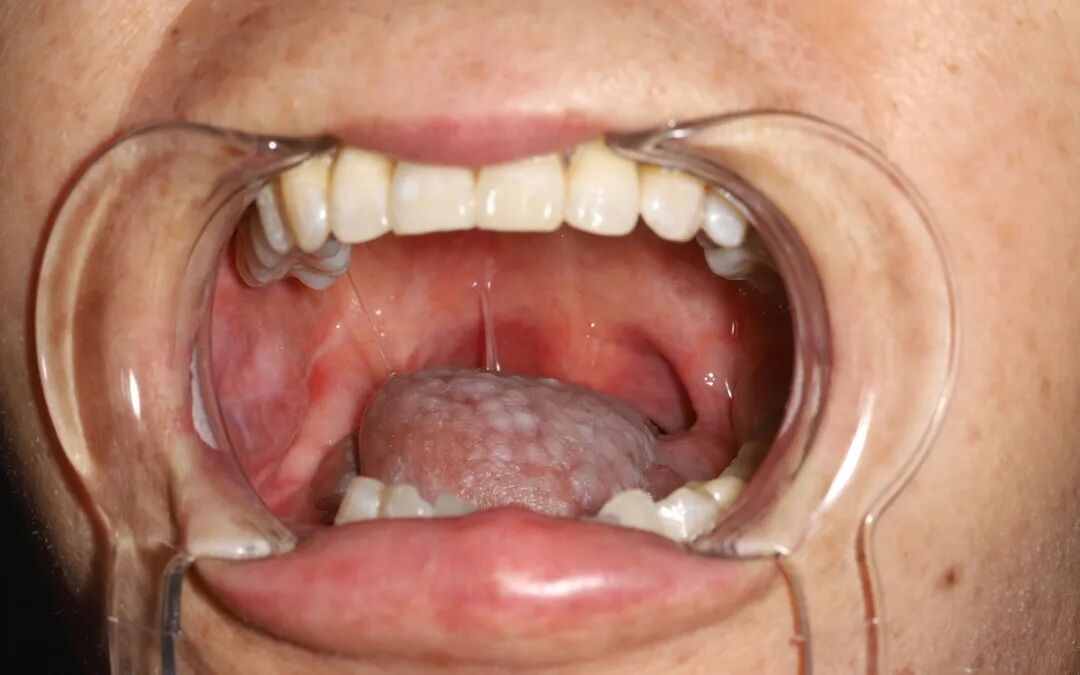

周大娘发现舌头上有类似“花生米”的肿块,半年多了舌头一直轻微的疼痛,肿块逐渐增大,吃饭喝水也感觉比较困难。周大娘去附近的医院就诊被诊断为局部晚期舌癌,后面转到中国医学科学院肿瘤医院深圳医院治疗。

头颈外科学科带头人魏明辉教授接诊后,考虑到舌癌术后会对患者讲话、咀嚼及吞咽功能造成一定的影响,外观上也会有所改变,无法保证生活质量。

考虑再三,魏明辉教授团队为其进行舌癌根治加游离股动脉穿支皮瓣手术,也就是在扩大切除周大娘五分之四舌头及肿瘤的同时,将大娘大腿内侧的皮瓣“嫁接”到残留的舌头上,尽可能保留了舌头的外观和功能完整性,后续周大娘的生活没有产生太大的影响。

△患者术后口腔皮瓣生长图与

大腿皮瓣供区切口缝合图

周大娘在术后10天顺利出院。经过复查,周大娘大腿皮瓣供区切口隐蔽,不影响下肢运动和感觉。